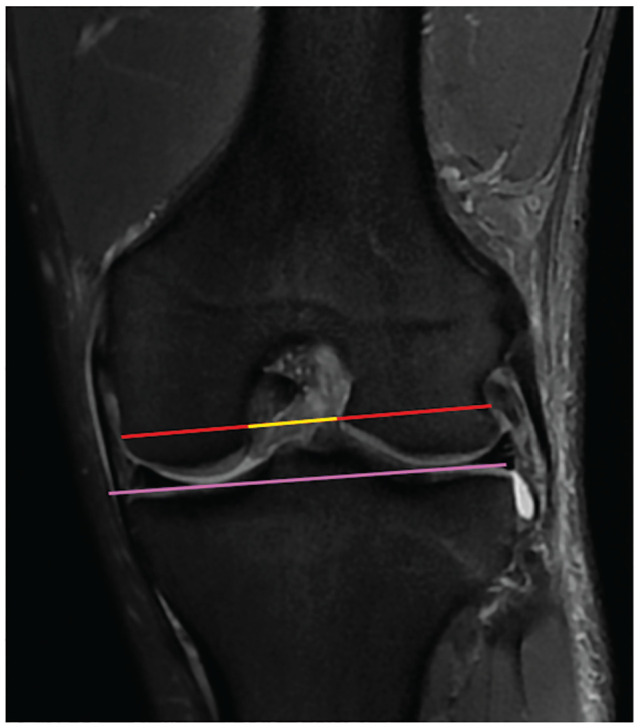

Methods: Patients ≥14 years of age with a confirmed ACL injury on MRI were included for review. Two orthopaedic resident physicians measured the NWI using both axial and coronal cuts using previously described measurement criteria as well as a modification utilizing the MRI cuts with the widest bicondylar width. The NWI was computed and a t test was performed to compare the axial and coronal measurements. Interobserver reliability was assessed using 2-way mixed intraclass correlation coefficients (ICCs).

Results: A total of 64 patients with ACL injuries were included. Modified axial and coronal NWIs for the cohort were a mean ± SD of 0.27 ± 0.02 and 0.23 ± 0.02, respectively. Modified axial NWIs were greater than coronal NWIs (P < .001). Standard axial and coronal NWIs for the cohort were 0.29 ± 0.03 and 0.25 ± 0.03, respectively. Standard axial NWIs were greater than coronal NWIs (P < .001). Modified axial and coronal NWIs for male and female patients were not different (P = .61 and P = .14, respectively). Axial notch width measurements were greater than coronal notch widths for both modified and standard measurements (P < .001). Axial intercondylar distances were not different from coronal intercondylar distances for both standard and modified measurements (P = .06 and P = .22, respectively). The ICCs for modified coronal and axial NWIs were 0.88 and 0.97, respectively. The ICCs for standard coronal and axial NWIs were 0.99 and 0.99, respectively.

Conclusion: NWIs were greater when measured on an axial MRI compared with the coronal plane for both measurement methods. This was because notch widths were measured wider in this plane since intercondylar distances were not statistically different.